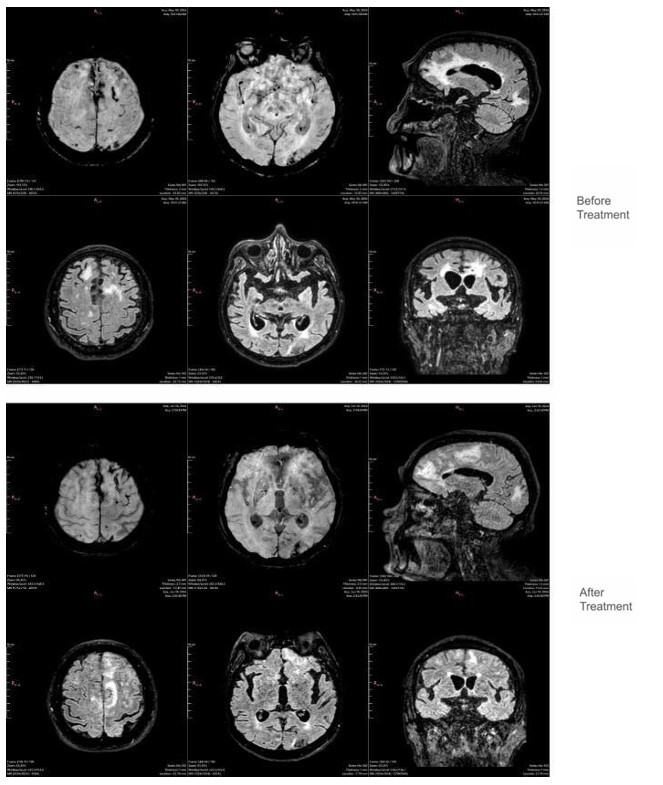

脑淀粉样血管病(CAA)是一种与β-淀粉样蛋白(a β)沉积在皮质和小脑膜血管相关的小血管疾病。传统上通过侵入性方法诊断,现在可以通过先进的成像模式来识别,提高了非侵入性诊断的准确性。一部分患者表现出炎症性表现,称为炎症性脑淀粉样血管病(CAA-RI),其特征是认知能力下降、行为改变和神经功能障碍。本研究重点介绍了两例CAA-RI,其亚急性发作,详细的临床进展,独特的MRI结果符合修订的诊断标准,能够早期怀疑。两例患者在免疫抑制治疗后均有显著改善,这加强了CAA-RI的潜在可逆性和早期识别的重要性。这篇文章强调了先进的影像学在CAA鉴别诊断中的重要性,以及通过及时治疗改善患者预后的潜力。

Cerebral Amyloid Angiopathy (CAA) is a small vessel disease associated with β-amyloid (Aβ) deposition in cortical and leptomeningeal vessels. Traditionally diagnosed through invasive methods, it can now be identified via advanced imaging modalities, enhancing non-invasive diagnostic accuracy. A subset of patients exhibits an inflammatory presentation, termed Inflammatory Cerebral Amyloid Angiopathy (CAA-RI), characterized by cognitive decline, behavioral changes, and neurological deficits. This study highlighted two cases of CAA-RI with subacute onset, detailed clinical progression, and distinct MRI findings consistent with revised diagnostic criteria, enabling early suspicion. Both cases showed significant improvement with immunosuppressive therapy, reinforcing the potentially reversible nature of CAA-RI and the importance of early recognition. This article underscores the relevance of advanced imaging in the differential diagnosis of CAA and the potential for improved patient outcomes with timely treatment.